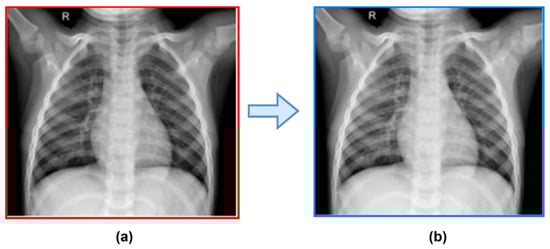

3.2.1. Pre-Processing Steps